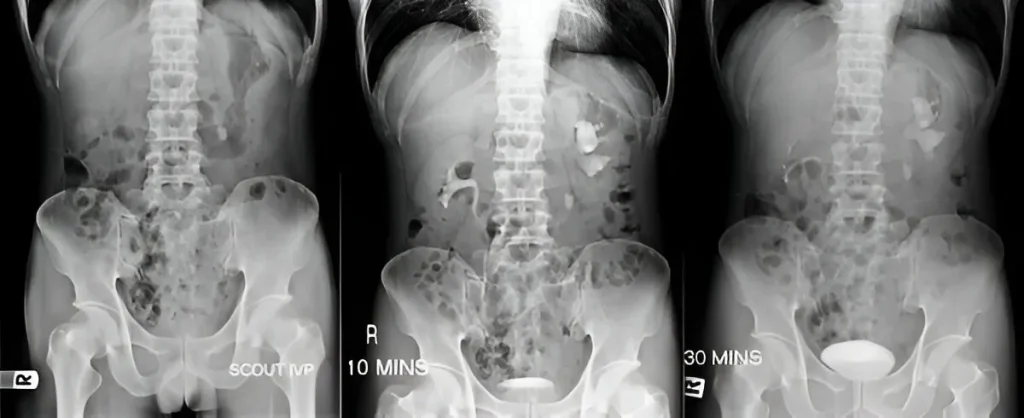

CT IVU/IVP in Navi Mumbai | Henotic Diagnostics

Looking for a reliable CT IVU/IVP in Navi Mumbai? At Henotic Diagnostics, Kharghar, we provide accurate CT Intravenous Urography and Pyelography to evaluate kidneys, ureters, and bladder with advanced imaging technology. Moreover, our expert radiologists ensure precise diagnosis for urinary tract disorders. In addition, we maintain patient comfort with safe, low-dose protocols. Therefore, when you need trusted CT IVP and CT IVU Near You, Henotic Diagnostics is your preferred choice in Navi Mumbai.